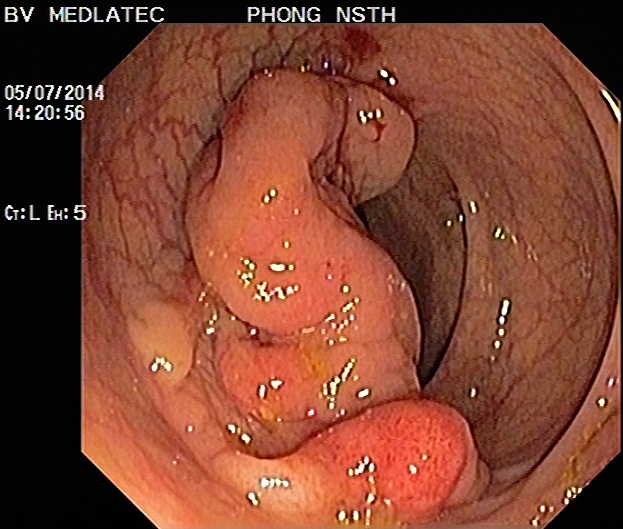

Hình ảnh polyp đại trực tràng

Hình ảnh ung thư đại trực tràng